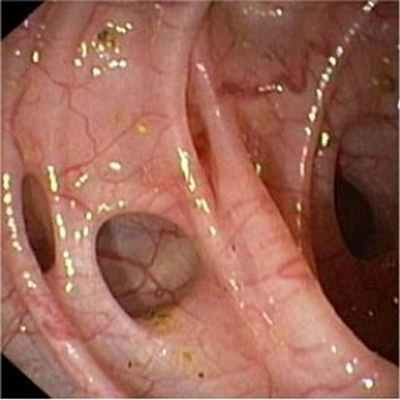

- Колоноскопия позволяет выявить наличие множественных дивертикулов, признаков воспаления или кишечного кровотечения, а также может оказаться полезной для обнаружения таких сопутствующих поражений как полипы и рак.

В диагностике заболевания вне осложнений наиболее ценными являются рентгенологические (ирригоскопия с ирригографией) и эндоскопические (ректороманоскопия, колоноскопия). Таким образом, возможность проявления тяжелых осложнений требует своевременной диагностики и лечения дивертикулярной болезни.

Клинические проявления дивертикулеза толстой кишки и его осложнений не могут служить основанием для установления точного диагноза заболевания. Диагностика и дифференциальная диагностика дивертикулеза толстой кишки основывается на анализе клинических проявлений заболевания и результатах обязательного рентгенологического и эндоскопического исследований толстой кишки.